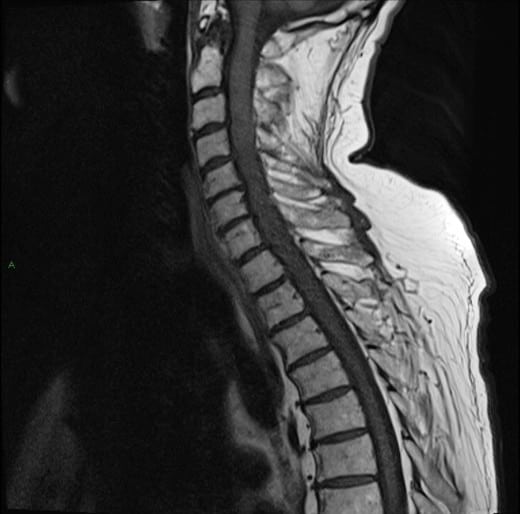

U tủy sống

» Thông tin: Nam giới – 70 tuổi.

» Lâm sàng: Yếu vai phải.

# U sao bào tủy sống (Spinal Astroctyoma) ngang mức C2-C4.